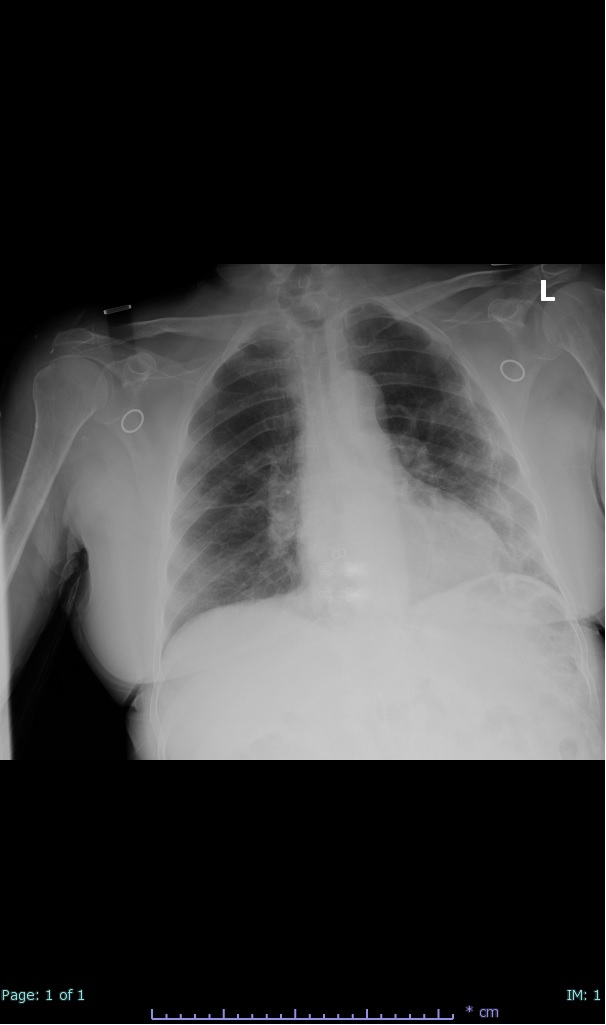

- 100% subpleural involvement, 33% + centrolobular involvement

- 66% had some + CXR finding I could correlate to a CT finding

- 66% had documented exposure, rest I couldn't find either way

I'll list age decade and + exposure documented #covid19 #coronavirus #radiology #FOAMed #radres 2/17